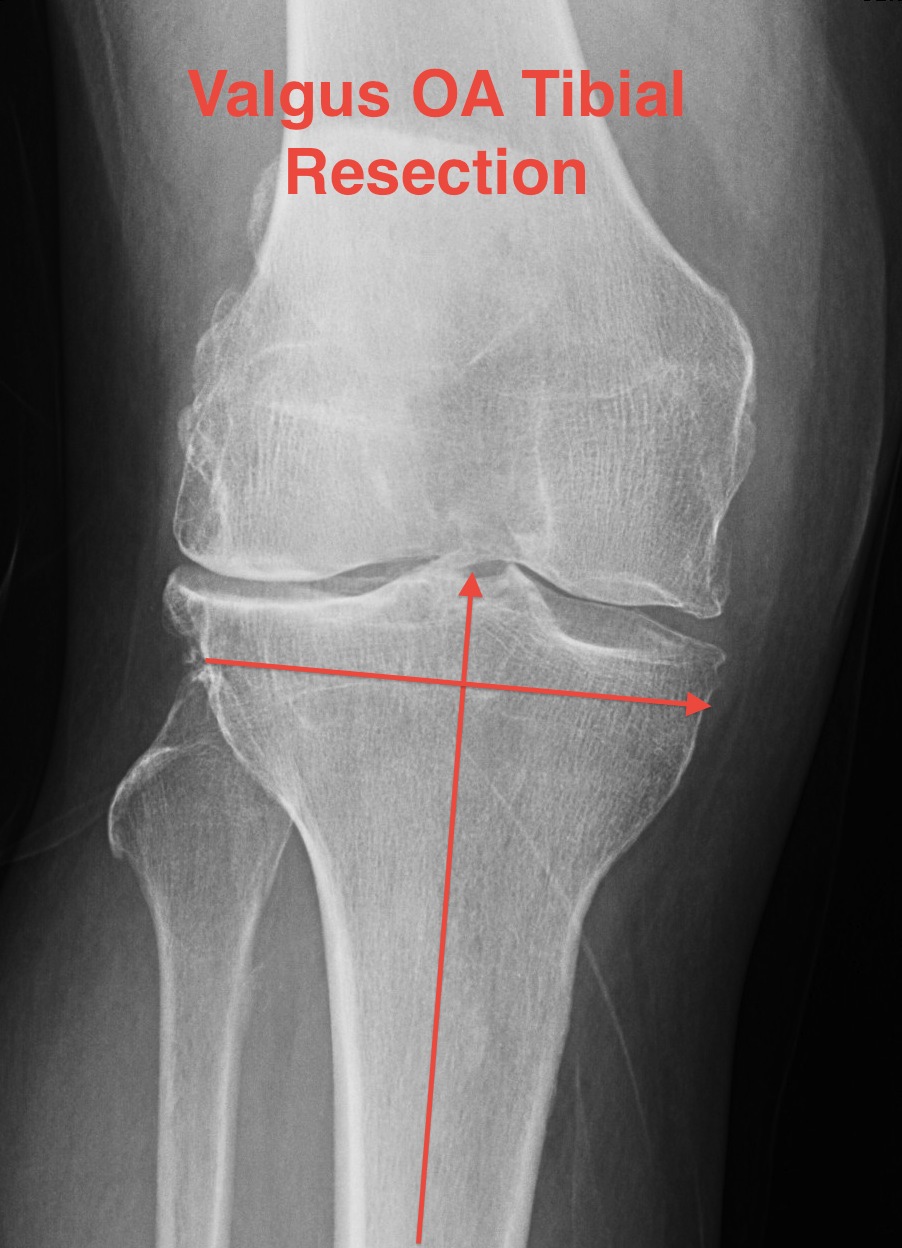

Tibial resection

- don't take 10 mm as bone worn laterally in valgus OA

- can't take 2mm off medial side as is the normal side

- need to estimate

- take 6 mm from lateral tibia intially, stay above fibula head

- much more symmetric proximal tibial resection

- use trial blocks to assess flexion / extension gaps

TKR Valgus OA Tibial Resection

Deficient lateral tibial plateau

- don't take > 10 mm medial plateau

- will get down into soft bone

- preop plan

- may need augments laterally and therefore stems

- below xray is borderline / but just ok